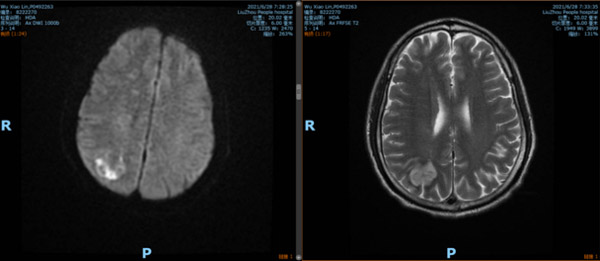

一個月前,在我院內分泌科住院的糖尿病患者吳某出現左側手腳無力的癥狀,且越發嚴重,經MRI(磁共振)檢查,診斷腦梗死,右側頸內動脈顱內部位閉塞,隨即轉入神經內科進行治療。

患者年紀較輕,右側大腦半球缺血嚴重,有開通閉塞血管的指征,恢復腦組織正常供血。但手術也存在一定風險,首先,患者此次發病不僅有腦細胞缺血壞死,而且由于缺血嚴重,顱內血管也出現缺血損傷,部分血液滲入腦梗死部位,形成出血轉化,如果這個時候把血管開通,出血的風險很高。其次,由于被斑塊完全堵塞的顱內血管很細,僅僅有2.5mm,再加上血管壁很薄,使得手術的難度激增,施術者的手在術中發生哪怕微微一點抖動,都有可能造成擴張血管破裂,造成致命的后果,這對于施術者而言,在心理和技術上,都是一種嚴峻的考驗。

經過謹慎評估,先給患者藥物治療,待血管修復后擇期開通閉塞血管。在患者進行藥物治療的一個月時間內,高文每天都惦記著這件事兒,細致準備,反復演練,通過高分辨率磁共振結果分析血管斑塊,進行評估。同樣的步驟在腦海中不知道重復了幾十遍,他經常失眠,眼睛一閉就回想起手術的細節,如同在刀尖上行走,容不得半點閃失。